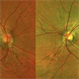

- Angioid Streaks

- 50 YEAR OLD FEMALE WITH NO SYSTEMIC ILLNESS WITH A CLASSICAL PICTURE. VISION REMAINS 6/6. THE FELLOW EYE HAS A SUBFOVEAL SCARRED CHOROIDLA NEOVASCULAR MEMBRANE.